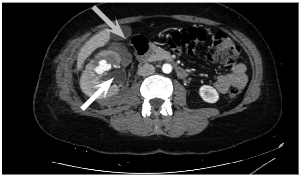

Cause of hematuria had to be determined, therefore urgent contrast enhanced computed tomography was performed (Figure 2) – contrast extravazation was found on the lower third of the right kidney (area of surgery), along with subcapsular hemathoma. Right hydroureteronephrosis and fluid in pelvis were observed. Blood clots and a small amount of contrast in the bladder were seen.

Right femoral artery was punctuated under local anesthetic. Inferior segmental artery was selectively catheterized and pseudoaneurysm was visualized. A microcatheter was inserted into segmental branch (Figure 4).